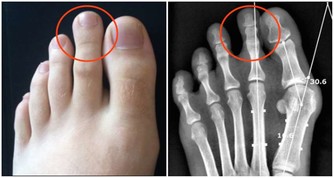

降低風險和並發症的一個好方法是,與你的醫生建立良好的關係。通常情況下,他會將你轉介給其他醫生:眼科醫生,足病醫生,心髒病專家,內分泌科醫生等。接受相關健康檢查,有助於採取預防措施,減少糖尿病並發症。